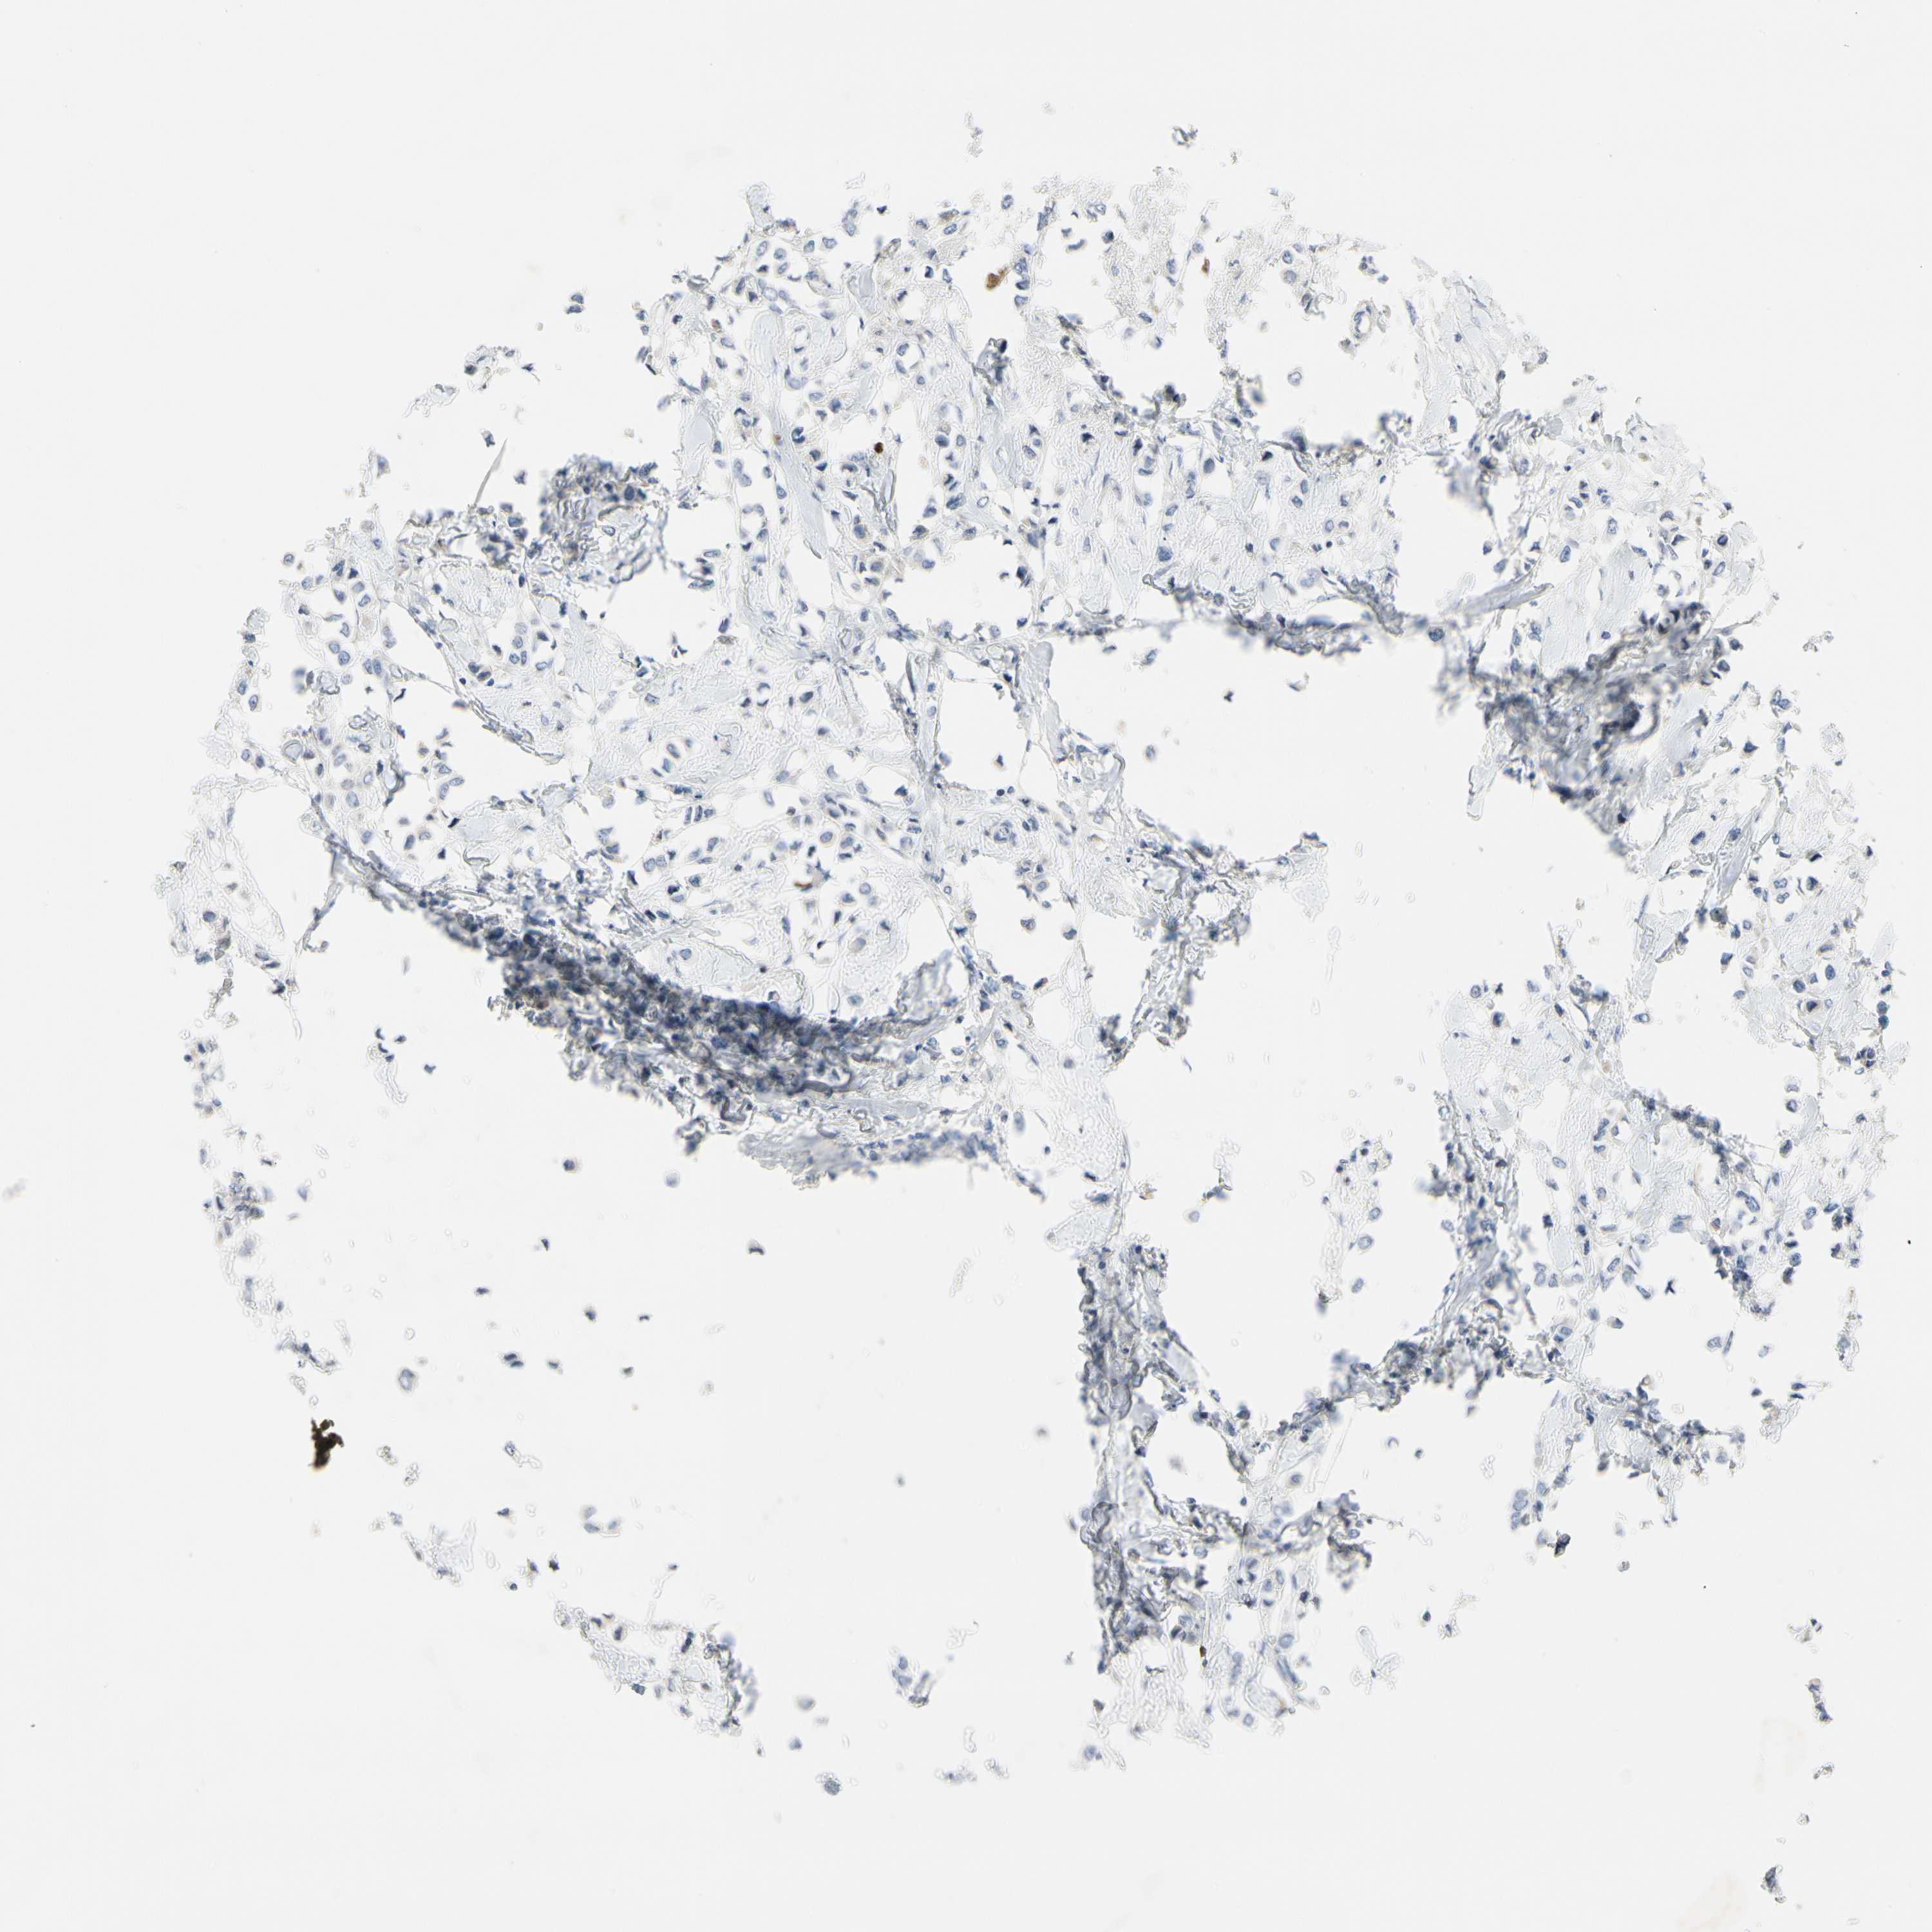

CANCER BREAST CANCER Show tissue menu

BRCA TCGA BRCA VALIDATION PROTEIN EXPRESSION